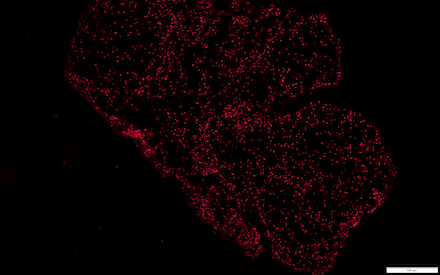

Methods: We selected markers for each of the components of NETS: (1) a granule protein, myeloperoxidase (MPO), (2) citrullinated histone 3 (CitH3), and cellular nucleic acid (NA, using Hoechst 33342). This was a single-blind study using cryopreserved thrombi from 30 patients, 15 with AF. Stroke thrombi were collected over a two-year span, and immediately frozen to -80*C post-thrombectomy. To capture the coverage of NET markers more comprehensively for each patient, we used cryostat to sample four sections (five-micron thickness) from each thrombus. We then fixed sections with 4% formaldehyde in phosphate buffered saline (PBS), performed immunohistological staining, and quantified extent of staining using ImageJ. Data for each NET marker from a single thrombus is represented as the mean percentage of thrombus area staining positively across the four corresponding sections. After performing Shapiro Wilks test for normality, statistical comparisons of NET marker staining coverage between AF and non-AF thrombi were performed with either unpaired T test or Mann-Whitney U test, depending on whether a parametric or non-parametric test was appropriate.

Results: Thrombi from patients with AF had greater MPO coverage(17.9 +/- 1.47% versus 11.6 +/- 1.29% in non-AF, p<0.01) and CitH3 coverage(12.6 +/- 1.46% versus 7.4 +/- 1.11% in non-AF, p<0.01). Staining for nucleic acid with Hoechst 33342 trended toward higher coverage in AF but did not reach significance (27.8 +/- 3.35% versus 22.6 +/- 3.20% in non-AF, p=0.30).